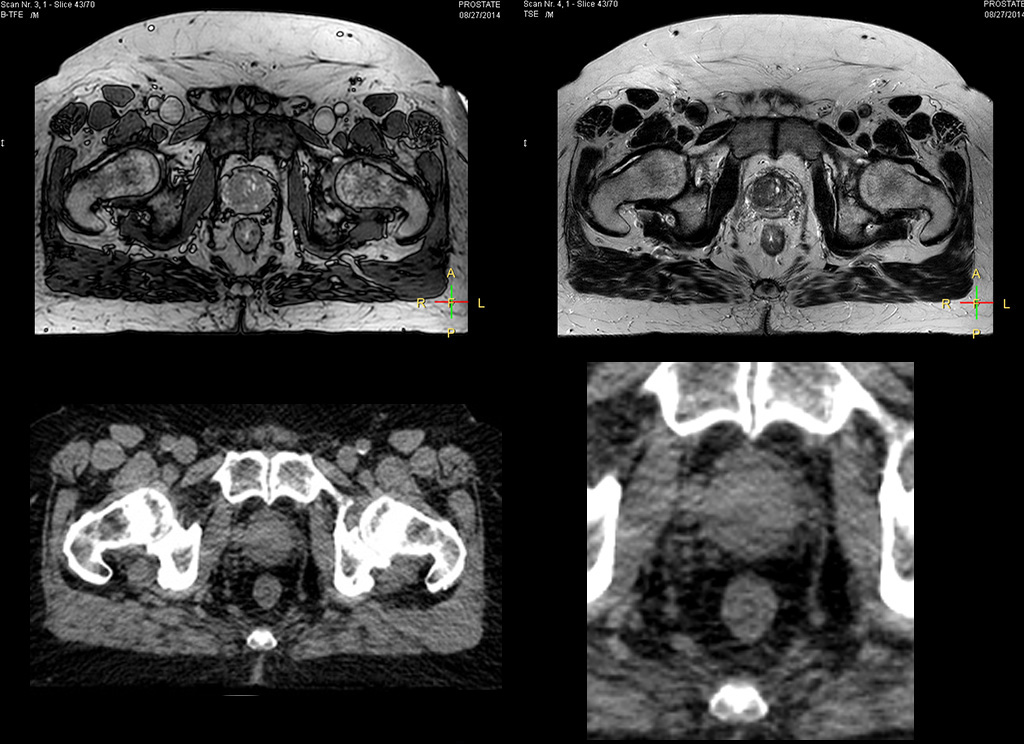

“The biggest problem for CT-based planning, especially in prostate, is you can’t see the cancer very well,” says Dr. Stevens. “On CT it can be quite challenging to see the edge of the prostate especially at the apex. When the edge of the prostate can’t be delineated well on CT, radiation oncologists will increase their margins a little bit so they don’t miss it, but that can also increase toxicity.” “Using MR, the prostate is well delineated. We quickly see the edges of cancerous tumors like in prostate cancer, and as normal structures can be defined, we can optimize the treatment plan to protect these organs and their normal function. This can potentially improve the outcome. And it improves workflow as well. We can contour more quickly, confident that the tumor is going to be in the field.” “The Ingenia 3.0T MR scanner provides high resolution allowing us to make scans fast for the patients. It also gives the potential to include methods like MR spectroscopy and diffusion weighted Imaging, which we’re in the process of doing right now,” Dr. Stevens adds.

“When a patient registers, first CT simulation and MR simulation are done, followed by CT-MR registration on Pinnacle3. Then the target and normal organ delineation is performed on MR images. Meanwhile we create a reference CT image for online treatment and localization correction. During the treatment phase we can perform additional MRI scans to visualize the anatomy changes and create an adaptive plan. This plan basically adapts the treatment plan to the changes.” “Along with its great benefits, MR has introduced some new challenges,” Dr. Stevens says. “Radiation therapy teams generally have no experience with MR. The Philips training helped us to implement fully the things we can do with the Ingenia MR-RT system. So the training, as well as having a good MR physicist, is critical.”

“There are some general challenges in RT imaging – even with CT – such as imaging geometry and positioning accuracy. Positioning is extremely important in RT, because we need reproducibility between imaging and treatment position. We also need accurate geometry so we can be sure our treatment plan is properly delivered during the treatment,” says Dr Yan. “The Ingenia MR-RT configuration includes an external laser positioning system for patient alignment and a flat tabletop for imaging the patient in treatment position. Ingenia MR-RT also came with a special QA package for regular monitoring of precision. Our Ingenia 3.0T scanner achieves good geometric accuracy – within a millimeter for most patients – and the phantom measurement is even better,” he adds. “Ingenia’s wide 70 cm bore is valuable to easily accommodate immobilization devices needed in RT,” says Dr. Stevens. “With a small bore MR scanner you can’t get the RT immobilization devices into the scanner properly; the large bore makes it easy to image patients in their immobilization device.”